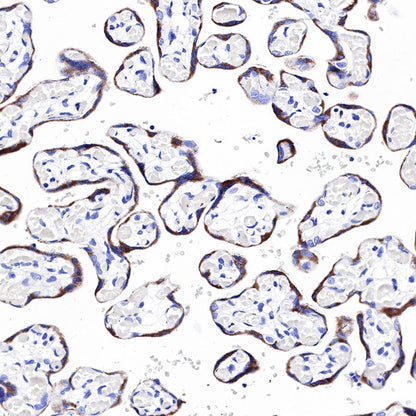

IHC shows positive staining in paraffin-embedded human placenta. Anti-PAPP-A antibody was used at 1/1000 dilution, followed by a HRP Polymer for Mouse & Rabbit IgG (ready to use). Counterstained with hematoxylin. Heat mediated antigen retrieval with Tris/EDTA buffer pH9.0 was performed before commencing with IHC staining protocol.